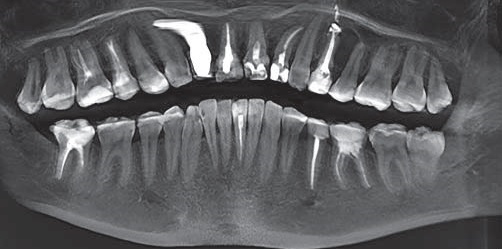

У мужчин и женщин средней возрастной группы эндодонтопародонтальные поражения были диагностированы у 57 из 312 обследованных мужчин и у 41 (19,43%) из 211 обследованных женщин соответственно (рис. 3). В этой возрастной группе, независимо от пола, определялся удовлетворительный индивидуальный уход за полостью рта (индекс гигиены 1,97±0,17 у. е.) и средняя тяжесть течения патологии пародонта (индекс КПИ=2,43±0,25 у. е.).

Рис. 3. Срез 3D – томограммы: эндодонтопародонтальное поражение верхней челюсти на уровне верхних левых премоляров и моляров у пациента М., 55 лет